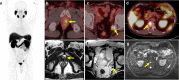

Results: We reviewed 57 original research articles during the period 2016-2021: 14 articles regarding the radiotracer PSMA; 18 articles regarding the primary tumor detection, local tumor staging, managing local recurrence; 17 articles for managing lymph node metastases; and eight articles for managing bone and other distant metastases. PSMA PET could be complementary to mpMRI for primary prostate cancer localization and is particularly valuable for PI-RADS three lesions. PET-MRI is better than PET-CT in local tumor staging due to its specific benefit in predicting extracapsular extension in MRI-occult prostate cancer patients. PET-MRI is likely superior as compared with PET-CT in detecting local recurrence, and has slightly higher detection rates than PET-CT in lymph node recurrence. PET-CT and PET-MRI seem to have equivalent performance in detecting distant bony or visceral metastases.

Conclusion: In conclusion, PET-MRI is suitable for local and regional disease, either primary staging or restaging, whereas PET-CT is valuable for managing distant bony or visceral metastasis.